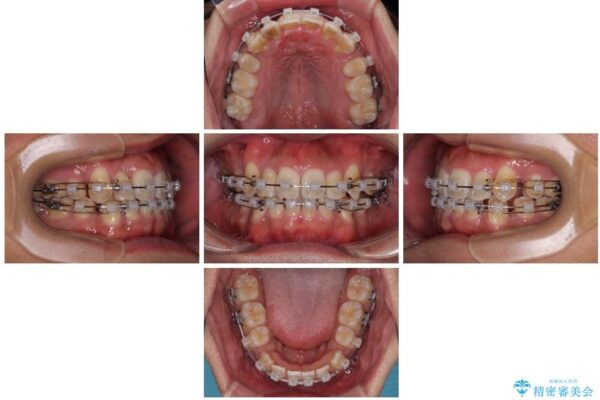

治療途中

• 八重歯と前歯のガタガタを抜歯矯正で治療|クリアブラケット使用例 治療途中画像

矯正装置は、審美性と費用面のバランスを考慮して、プラスチックブラケットとメタルワイヤーを使用しました。

透明感のあるブラケットを用いたため、従来の金属装置よりも目立ちにくく、日常生活での見た目の不安も軽減できます。